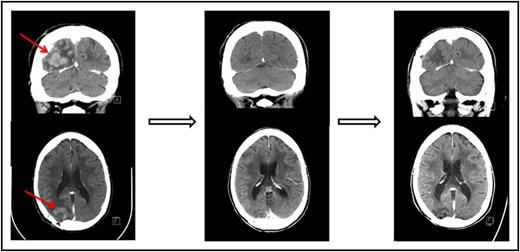

One of the patients who achieved a complete response to nivolumab had primary refractory PCNSL (Figure 1 and Table 1, patient 1). One patient who achieved only a partial response to prior WBRT had a further decrease in enhancing disease on nivolumab therapy (Table 1, patient 3). An additional patient who achieved only a partial response to prior focal radiation obtained a complete radiographic response to nivolumab with resolution of parenchymal and leptomeningeal involvement (Table 1, patient 5). This patient had persistent intraocular disease that was confirmed by vitrectomy and treated with ocular radiation (Table 1, patient 5).

Pre- and posttreatment head CTs with contrast in a patient with primary refractory PCNSL. (Left) The contrast-enhancing lesion before treatment with nivolumab. (Middle) Complete response following 2 months therapy with nivolumab. (Right) Continued complete response 13 months following initiation of therapy.